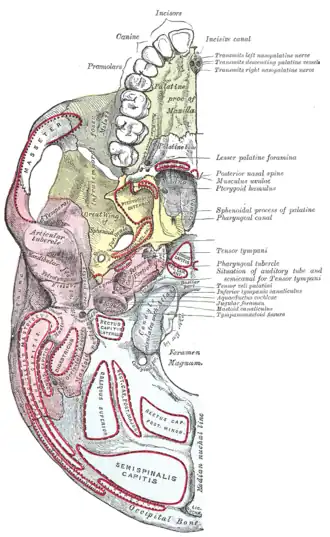

Base of skull. Inferior surface.

Base of skull. Inferior surface.